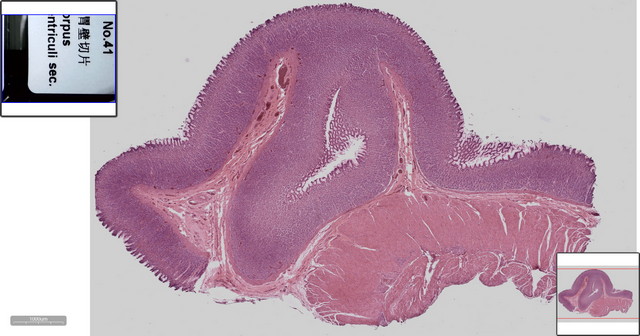

胃壁局部视野

胃壁切片数字切片(显示标签图)